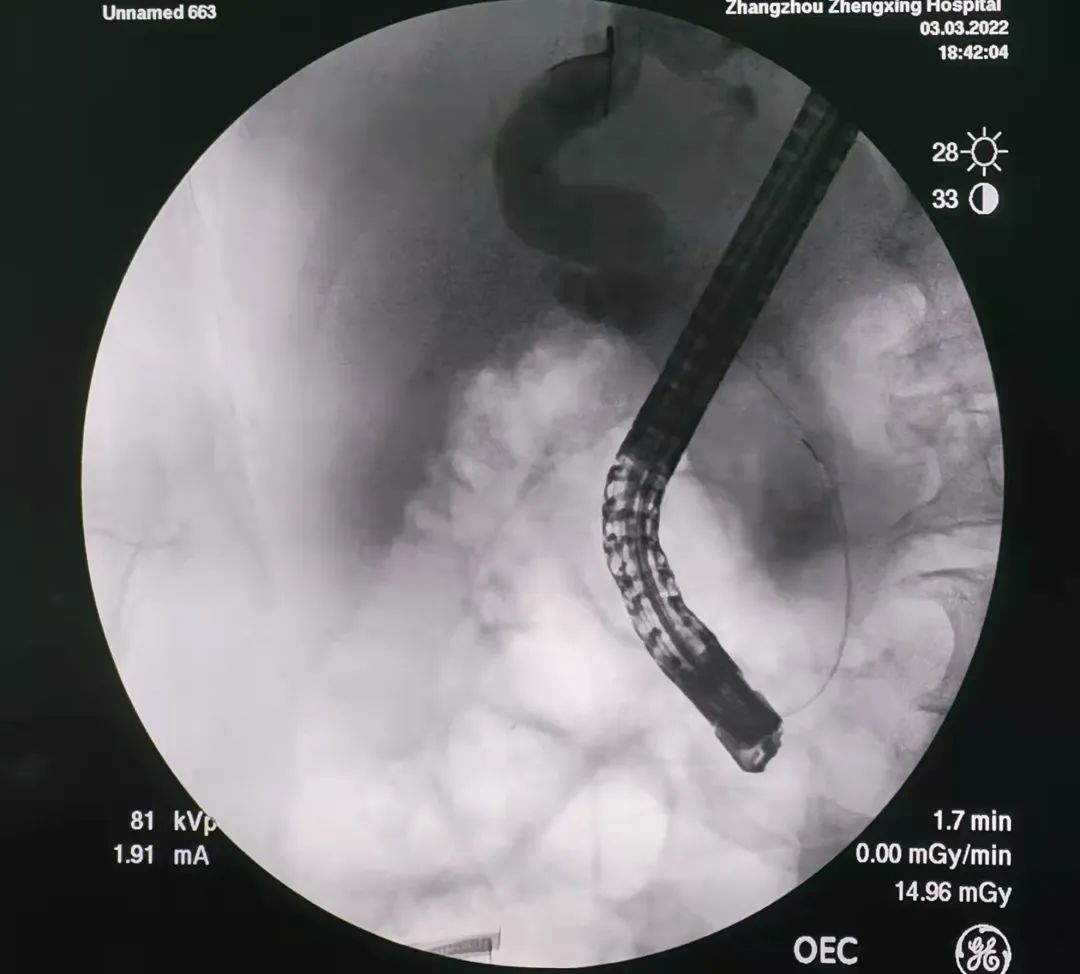

最終,在否定了幾種常規(guī)的檢查后,擬定患者獲益最大的方案:逆行胰膽管造影(ERCP)結(jié)合膽胰內(nèi)鏡進(jìn)行微創(chuàng)檢查及精準(zhǔn)活檢。

(膽管內(nèi)充滿大量白色膠凍樣物質(zhì),

但還是能清楚分辨腫瘤組織)

經(jīng)過一個多小時的手術(shù),通過膽胰內(nèi)鏡,消化內(nèi)科精準(zhǔn)定位腫瘤部位,直視下取到組織標(biāo)本(后經(jīng)病理檢查證實為原位癌)。

診斷明確,消化內(nèi)科團(tuán)隊共同探討出了解除膽道梗阻的手術(shù)方案。在患者和家屬知情同意后,消化內(nèi)科為患者定制了一根金屬支架,將被腫瘤組織占據(jù)的膽道出口撐開,解除梗阻,順利引出淤積的膽汁。經(jīng)過3天的觀察,患者的黃疸指標(biāo)已回落至接近正常水平。